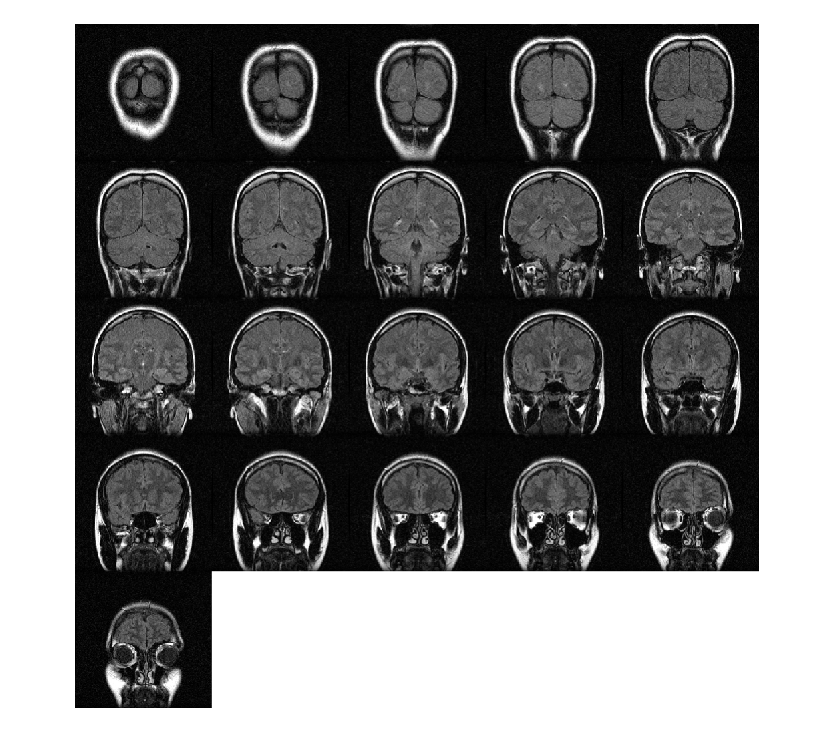

Загрузите объем MRI. Этот объем хранится как 4-D массив с одноэлементной размерностью. Создайте 3-D полутоновый объем при помощи squeeze функция, чтобы удалить одноэлементную размерность.

load mri;

V = squeeze(D);

Отобразите плоскости объема.

montage(D,'BackgroundColor','w')

Figure contains an axes object. The axes object contains an object of type image.